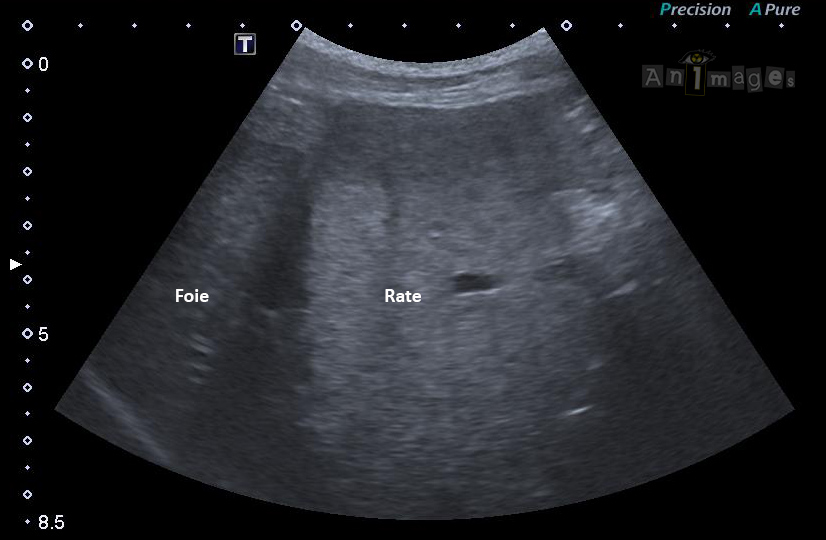

Approche sous-costale médiane